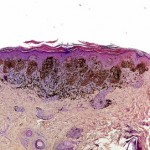

La psoriasi è una malattia autoimmune che colpisce circa 125 milioni di persone in tutto il mondo. I sintomi comprendono la formazione di lesioni infiammate, arrossate, squamose che compaiono sulla pelle e variano da lievi a gravi. La malattia è spesso associata ad altre condizioni di salute gravi come il diabete, malattie cardiache e depressione.

I ricercatori hanno osservato un aumento dell’ accumulo di cellule dendritiche plasmacitoidi nelle lesioni psoriasiche di pazienti, così come nei topi che sono organismi modello per lo studio della malattia. Cellule dendritiche plasmacitoidi sono un tipo specifico di cellule immunitarie che possono infiltrarsi nei tessuti danneggiati durante la fase precoce della psoriasi. Al contrario, i livelli di un altro tipo di cellule dendritiche conosciute come cellule di Langerhans, erano, nella sperimentazione, significativamente diminuite nelle lesioni, rispetto alla pelle sana negli esseri umani e nei topi. Quando i livelli di cellule dendritiche plasmacitoidi nei topi sono diminuiti durante le prime fasi della malattia, allora i sintomi della psoriasi sono stati soffocati. Una riduzione simile nelle cellule di Langerhans, in una fase precoce della malattia, non ha avuto alcun effetto. Se i livelli di cellule di Langerhans vengono ridotti in fasi avanzate della malattia, i sintomi della psoriasi vengono esacerbati.